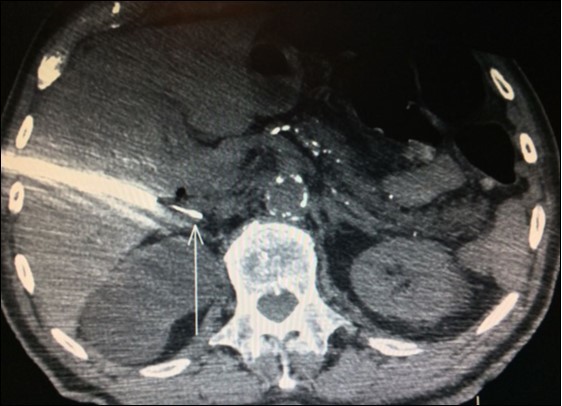

Adrenal biopsies (Figure 3) before adrenalectomy is useful in order to identify the nature of the lesion10,11,12. Even with fine-needle aspirate is possible a diagnosis and also a successful molecular testing by next-generation sequencing in order to the identification of pathogenic alterations linked to available or developing targeted therapies30.

Figure 3.Right adrenal needle biopsy (arrow)